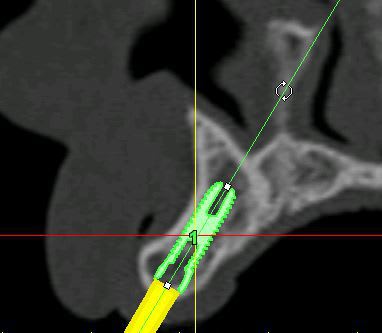

je mets les coupes et les radios post op...

intervention "quasi" flaless, juste des incisions crestales en W pour manager les papilles...

c'est un boulevard en épaisseur, ok...

l'intérêt...c'est qu'en une petite heure c'était plié, provisoires inclues...et sans ouvrir grand pour contrôler les proximités radiculaires et faire radio sur radio de contrôle pour ne pas toucher aux racines...